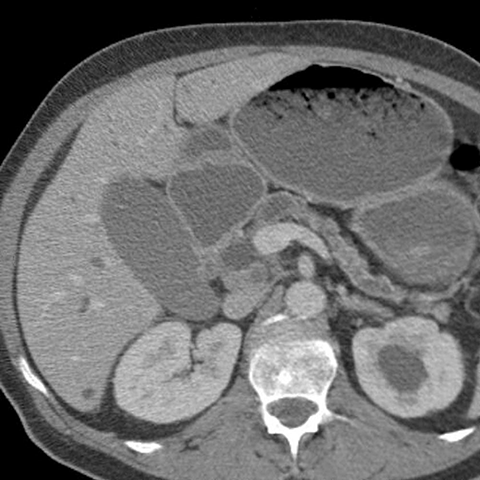

56 year-old male presents with painless jaundice [3 of 7]